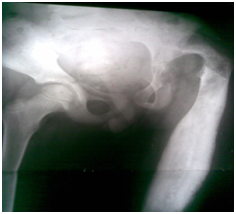

Figure 2 Across hip Naseer Awais External Fixator applied for control distraction of proximally migrated femoral head, 2mm per day.

Figure 3&4 Showing distraction started process is going on 2mm per day, to avoid Neuro-vascular injury.

Figure 5 showing Radiograph 3 weeks after distraction is on progress by applying NA Ex Fix.